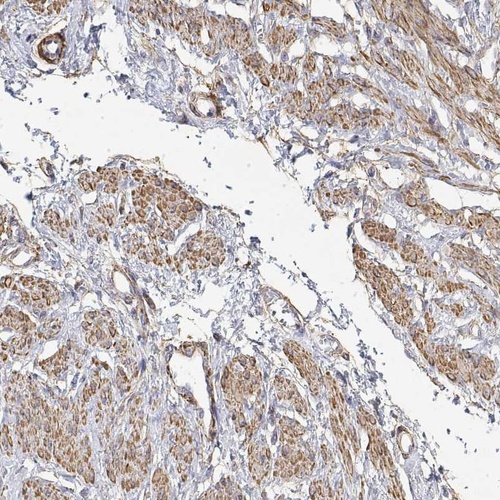

Immunohistochemical staining of human smooth muscle shows moderate cytoplasmic positivity in smooth muscle cells.